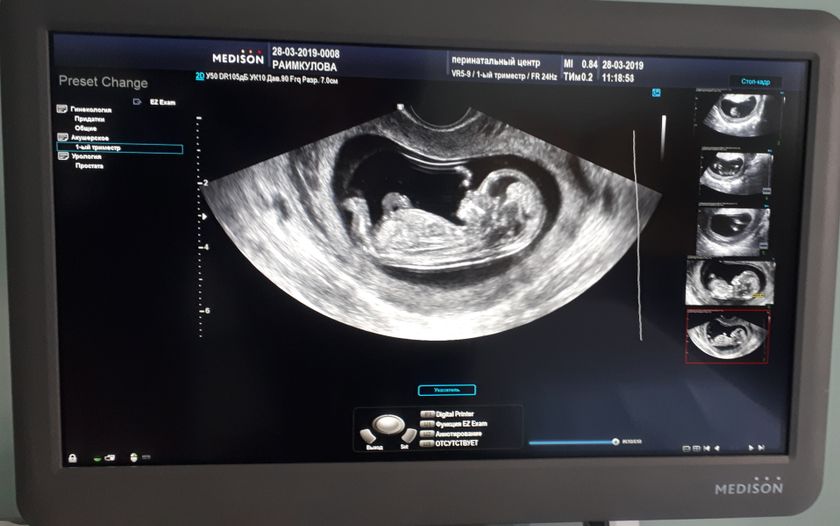

Я пока не знаю кто ты, но люблю уже безумно?… В целом всё у нас хорошо. Всё в норме. Срок на сегодня 12 недель и 1 день, как я и думала. Как только меня не вертел врач?вправо, влево, боком, ср@ком, чуть ли на голове не стояла, но увидеть кто же живёт во мне, так и не удалось. Будем ждать еще 10 недель. Но где-то глубоко в душе думаю, что это дочка?не знаю почему, но так кажется, а может я просто привыкла к девочкам, ведь у меня их 3?.

А никак не решались, не планировали. Вообще никогда не думала, что буду мамой четверых? но тут получилось… сама не пойму как, предохранялись. Сказать, что была в шоке, ничего не сказать. Долго думала, но на аборт так и не решилась. Домашние были против, а я сказала: буду рожать! Кому не нравится, можете поплакать в подушку!? Теперь уже до меня дошло, что у меня дубет 4! Глядя сегодня на манитор с узи, прям бабочки в животе полетели… Муж смерился и тоже уже ждет этого чуда?